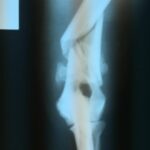

He was x-rayed and it was determined that he had likely been hit by a car and had a seriously fractured humerus, along with damage to the radial nerve. We decided to have the leg amputated. Iggy recovered from the surgery astoundingly quickly, and settled into life at his foster home without a hitch.